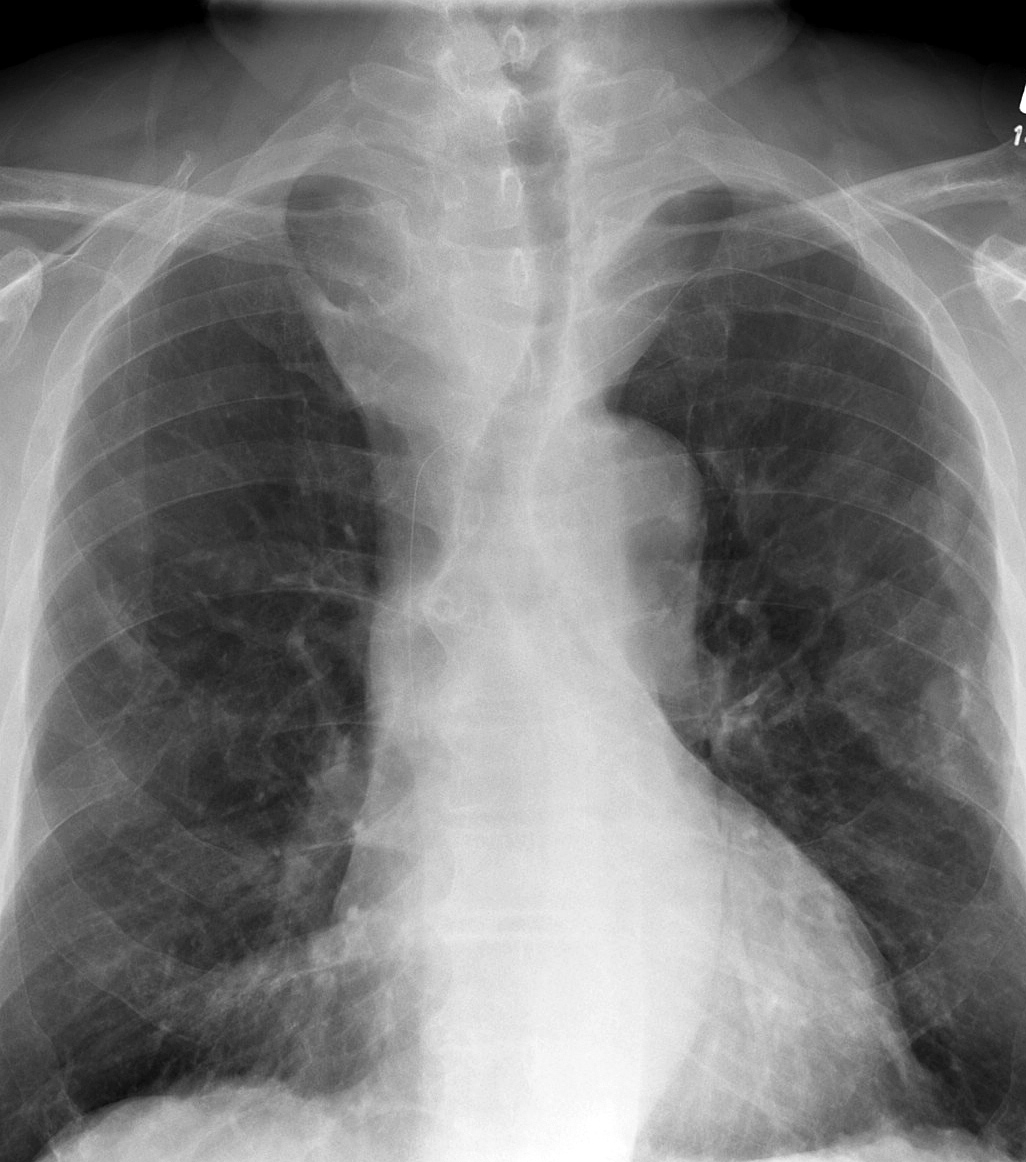

Mediastinum

Thyroid

Thyroid Mass Case 11 PA

Thyroid Mass

Case 11 PA